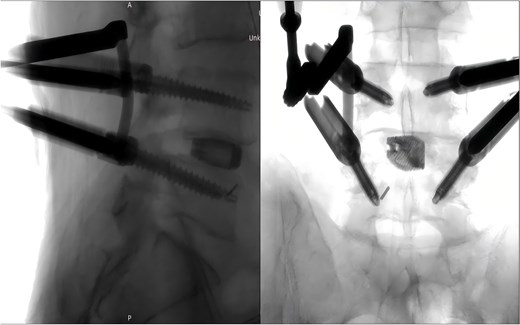

Following removal of the left L5 pedicle screw during the procedure, the smallest endoscopic sheath was inserted along with the endoscope to explore the screw trajectory. Under fluoroscopic guidance, endoscopic forcep was utilized to identify and grasp the fractured guidewire (Fig. 4). Tactile feedback of a metallic sensation confirmed precise localization. Approximately 6 mm of the fractured guidewire was successfully extracted (Fig. 5). Subsequent fluoroscopy confirmed complete removal of the broken guidewire. The left L5 pedicle screw was reinserted, and bilateral connecting rods were placed. The nuts were then securely fastened. Hemostasis was confirmed under endoscopic visualization, and the surgical incisions were closed and dressed with sterile coverings.